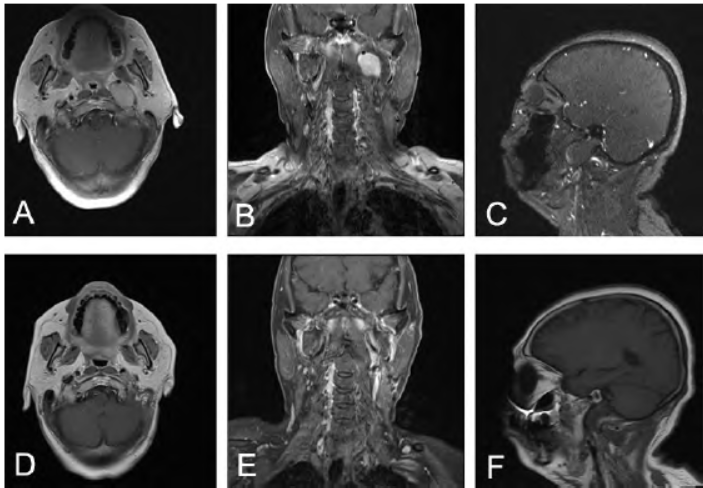

病例1:58岁女性,因声音嘶哑3个月于2022年1月2日入院。入院体格检查:左侧声带固定于旁正中位,右侧声带运动正常。甲状腺彩色超声多普勒、胸部CT、胃镜检查

均未发现占位性病变。头颅MRI示左侧咽旁间隙占位,经JF至颅后窝,大小4.5 cm×3.0 cm×1.8 cm,T1WI 呈等信号,T2WI 呈等-稍高信号(图1A~C),FLAIR呈高信号,边界清楚。

术前诊断:左侧JF区良性肿瘤。完善术前准备后,在导航辅助下显微手术切除JF区肿瘤,并行颅底重建。术中见肿瘤主体位于JF区,侵蚀JF区骨质,并导致JF扩大,压闭乙状窦,并少量突入桥小脑角,向前突入咽旁间隙,包膜完整。先部分切除肿瘤实质、缩小体积,然后沿肿瘤包膜内界面分离,最终全切除肿瘤(图1D~F)。

图1 左侧颈静脉孔区神经鞘瘤手术前后影像。A~C. 术前头颅MRI显示左侧颈静脉孔区占位性病变,大小4.5 cm×3.0 cm×1.8 cm,T1WI呈等信号,T2WI呈等-稍高信号;D~F. 术后3个月复查头颅MRI显示肿瘤无复发

术后病理显示:JF区梭行细胞肿瘤,免疫组化:CD34(血管+),Ki67(3%+),S-100多(+),SMA(血管+),Sox-10(+),结合免疫组化最后诊断为神经鞘瘤。术后有轻度饮水呛咳、经常性干咳,随访观察6个月,逐渐好转。